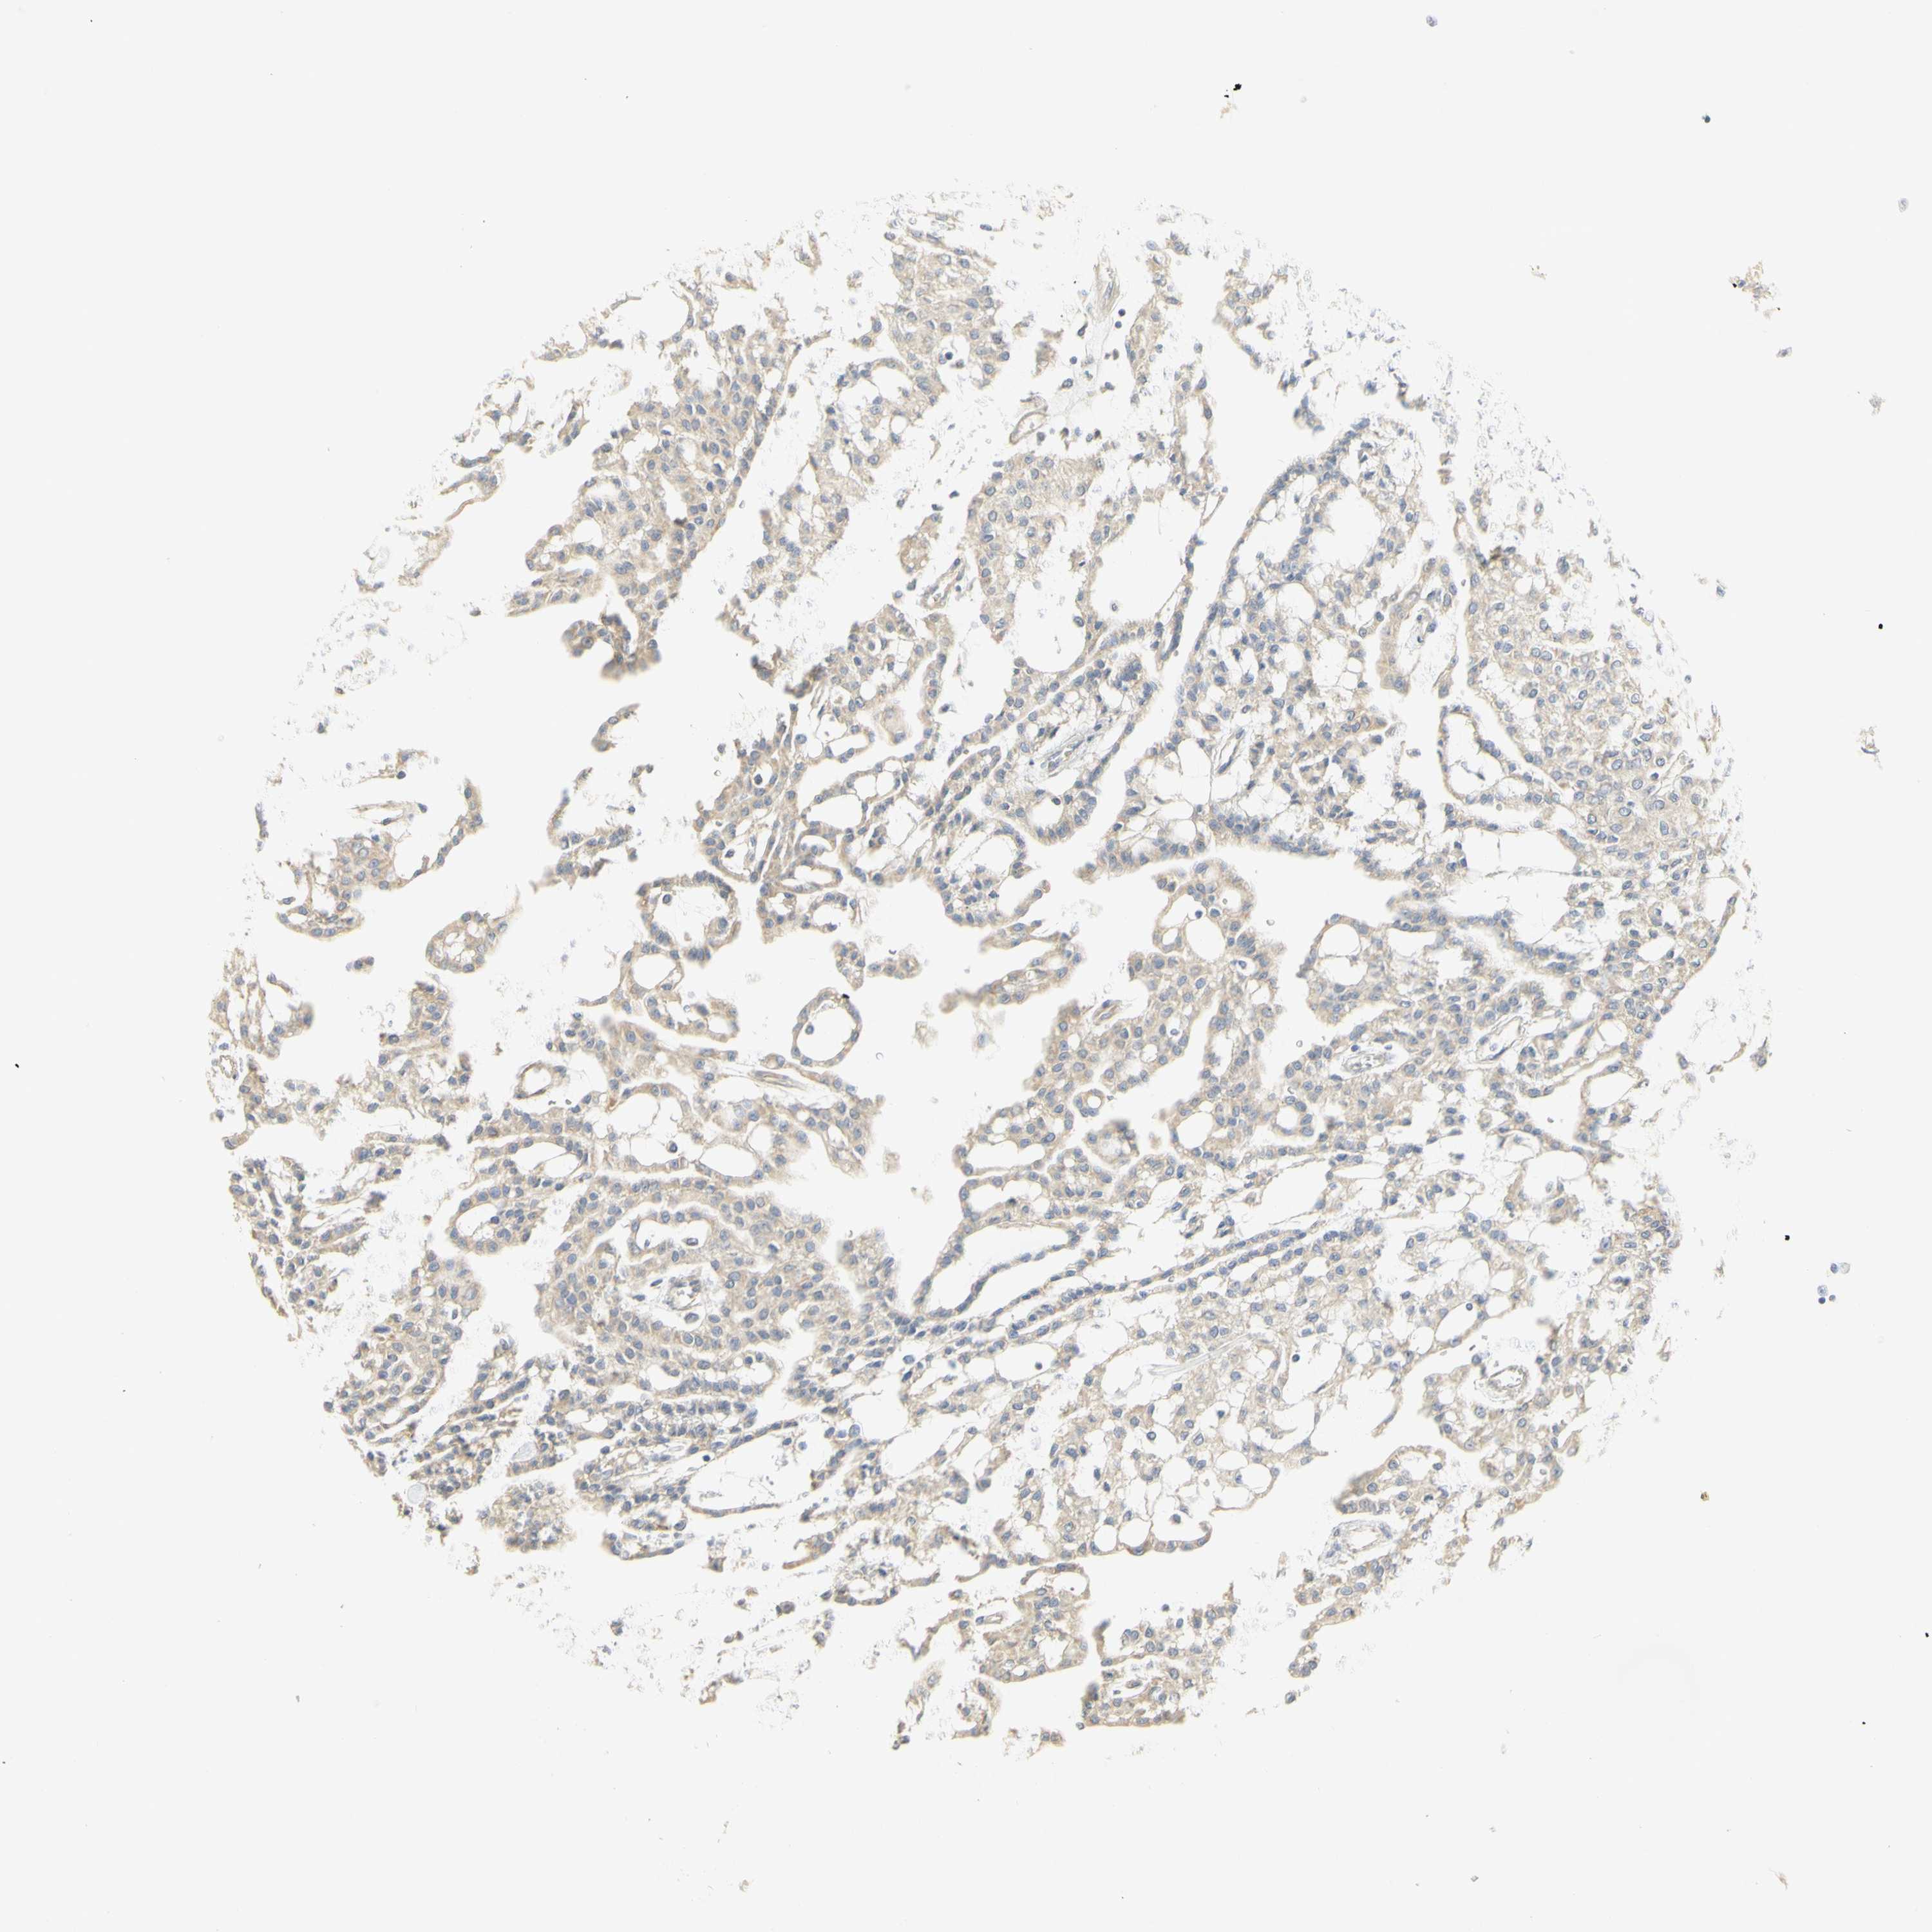

KIDNEY RENAL PAPILLARY CELL CARCINOMA (TCGA) - Interactive survival scatter ploti

The Survival Scatter plot shows the clinical status (i.e. dead or alive) for all individuals in the patient cohort, based on the same data that underlies the corresponding Kaplan-Meier plots. Patients that are alive at last time for follow-up are shown in blue and patients who have died during the study are shown in red.

The x-axis shows the expression levels (FPKM) of the investigated gene in the tumor tissue at the time of diagnosis. The y-axis shows the follow-up time after diagnosis (years). Both axes are complimented with kernel density curves demonstrating the data density over the axes. The top density plot shows the expression levels (FPKM) distribution among dead (red) and alive patients (blue). The right density plot shows the data density of the survived years of dead patients with high and low expression levels respectively, stratified using the cutoff indicated by the vertical dashed line through the Survival Scatter plot. This cutoff is automatically defined based on the FPKM cutoff that minimizes the p-score. The cutoff can be changed by dragging the vertical line or by entering a cutoff value in the square labeled "Current cut-off".

Under the Survival Scatter plot the p-score landscape (black curve; left axis) is shown together with dead median separation (red curve; right axis). Dead median separation is the difference in median mRNA expression between patients who have died with high and low expression, respectively. It is calculated as follows: median FPKM expression of dead patients with high expression - median FPKM expression of dead patients with low expression. This is intended to aid the user in visually exploring custom cutoffs and the associated p-scores and dead median separation.

Individual patient data is displayed and can be filtered by clicking on one or more of the category buttons on the top of the page. Categories describing expression level and patient information include: high, low, alive, dead, female, male and tumor stages. The scale of the x-axis can be toggled between linear and log-scale by clicking on the "x log" button. Mouse-over function shows TCGA ID, patient information and mRNA expression (FPKM) for each patient.

& Survival analysisi

Kaplan-Meier plots summarize results from analysis of correlation between mRNA expression level and patient survival. Patients were divided based on level of expression into one of the two groups "low" (under cut off) or "high" (over cut off). X-axis shows time for survival (years) and y-axis shows the probability of survival, where 1.0 corresponds to 100 percent.

KIF11 is potential prognostic, high expression is unfavorable in Kidney Renal Papillary Cell Carcinoma (TCGA)